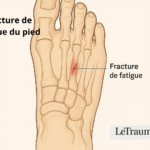

Traumatismes fréquents : entorses, foulures et micro-fractures méconnues

- Une entorse mal soignée peut créer une instabilité chronique.

- Certaines micro-fractures passent inaperçues à la radiographie initiale.

Radiographie de la cheville et du tibia

- Elle permet d’exclure une fracture, un arrachement osseux ou une arthrose articulaire.

IRM ou scanner

- Permet de visualiser les lésions osseuses, nerveuses ou ligamentaires invisibles à la radio.

- L’IRM est l’examen de choix en cas de doute sur une tendinopathie complexe ou une atteinte nerveuse.